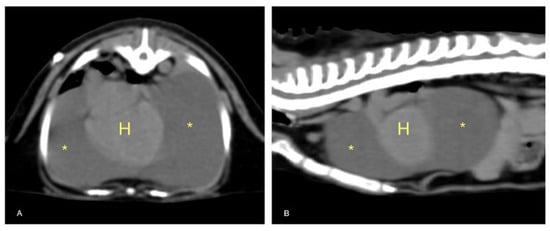

3.6. Postmortem Examination

Postmortem examination highlighted conjunctival, oral, and vulvar cyanosis. At skinning, there was severe and diffuse skeletal muscles congestion. The severely dilated pericardial sac almost completely occupied the thoracic cavity, causing severe and bilateral pulmonary compression (Figure 6). About 100 mL of yellowish-white, slightly turbid liquid was drained from the pericardial sac, where a fibrin clot was also identified. In the cranial mediastinum, surrounded by a moderate amount of adipose tissue, a severely enlarged lymph node was detected (Figure 7). In the abdominal cavity, along with moderate spleno- and hepatomegaly, the caudal vena cava was severely congested, and numerous hemorrhagic suffusions and petechiae were observed in the small intestine. Further pathological findings were congestion of jugular veins and severe, diffuse meningeal hyperemia.

Histology showed severe pulmonary hyperemia and atelectasis, associated with pulmonary edema, alveolar hemorrhages, rare intra-alveolar hemosiderophages, and mild multifocal compensatory emphysema (Figure 8). The thoracic duct was not identified during necropsy. Microscopic examination of the heart failed to detect significant pathological changes. The mediastinal lymph node was microscopically characterized by edema and severe hyperemia associated with a locally extensive hemorrhage (Figure 9). The hemorrhagic nature of intestinal lesions was confirmed histologically. Microscopic examination identified severe and diffuse hyperemia of hepatic centrolobular veins and allowed diagnosis as adenoma of the rete ovarii, a 4 mm nodule detected in the right ovary. Anatomopathological examination identified a cardiogenic shock, secondary to pressure changes developed in the thoracic cavity, as the most likely cause of death of the subject. This hypothesis is supported by the severe multi-organ congestion, caudal vena cava and jugular veins distension, and cyanosis of external mucous membranes.

Figure 6. Anatomopathological examination of the thoracic cavity. There is a severe dilatation of the pericardial sac with severe bilateral lung compression.

Figure 7. Thoracic organs. In the cranial mediastinum, surrounded by a moderate amount of adipose tissue, a severely enlarged lymph node (arrow) was detected.